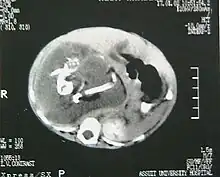

Tomografía retroperitoneal.